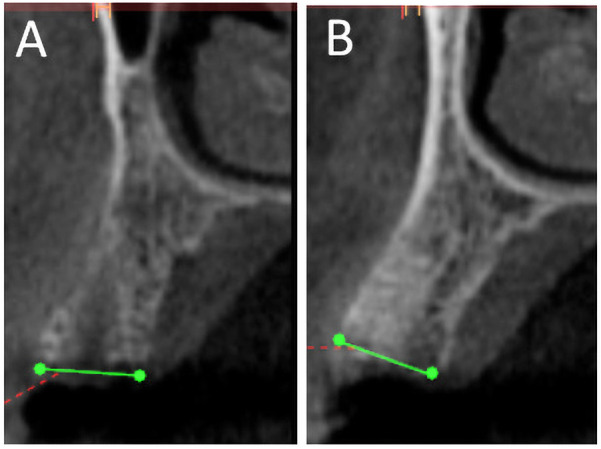

Materials and methods: Eighteen patients (6 males, 12 females; aged 23-45 years) requiring posterior tooth extraction were enrolled. Eighteen extraction sockets were augmented with either NuOss or Bio-Oss and covered with a collagen membrane. After six months, Cone Beam Cephalometry (CBCT) assessed dimensional changes in buccolingual width and buccal bone thickness. Bone core biopsies were obtained during implant placement and decalcified for histomorphologic examination. Statistical analysis compared dimensional changes and histomorphometric parameters between groups.

Results: All experimental sites healed uneventfully, with complete soft tissue healing within four weeks and successful implant placement. CBCT scans showed comparable, non-significant dimensional reductions. Histomorphologic examination revealed lamellar cortical bone and osteoid trabeculae with partial to optimal integration. NuOss demonstrated significantly higher new bone formation (52.5 ± 2.5%) compared to Bio-Oss (37.5 ± 2.5%; p = 0.0021), with lower residual graft material (27.5 ± 2.5% vs. 42.5 ± 2.5%; p = 0.0018). Bio-Oss grafted cases exhibited more pronounced inflammatory cell infiltration. Soft tissue proportions were similar between groups (NuOss: 22.5 ± 2.5%, Bio-Oss: 17.5 ± 2.5%; p = 0.0892).